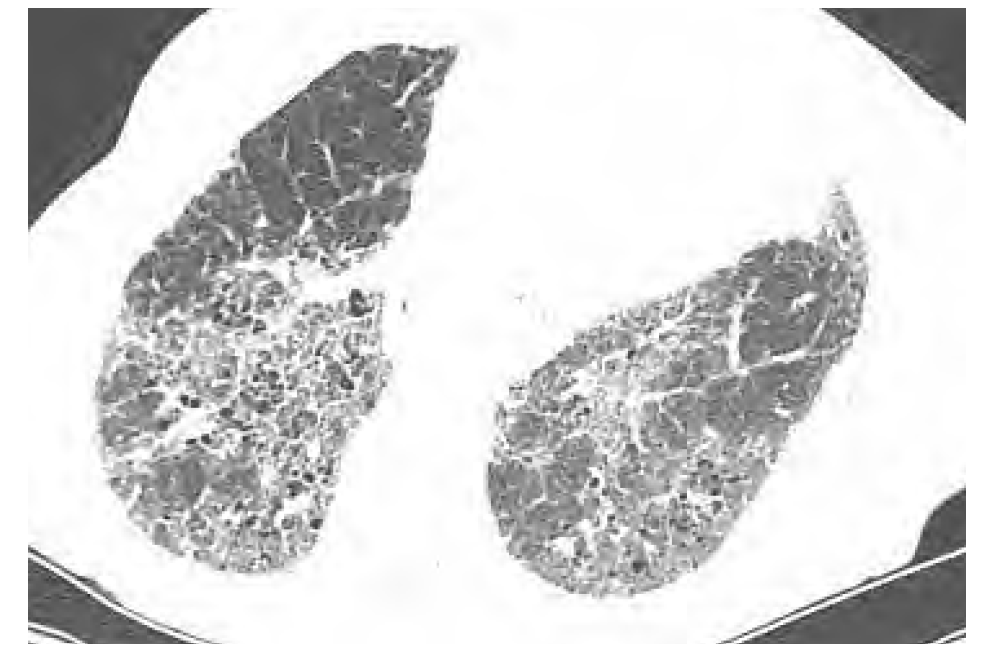

What is this? (What feature do we see?)

NSIP (micronodules?)